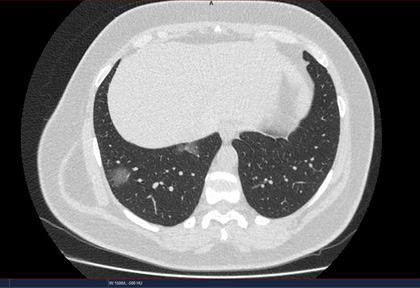

Routine clinical laboratory assays were performed in the hospital’s clinical laboratories. Clinical and laboratory information was extracted from the patients’ medical records. C reactive protein (CRP) in plasma was measured by immunoturbidimetry (Beckman Coulter, Krefeld, Germany). Interleukin-6 (IL-6) levels in plasma were measured by electrochemiluminescence (Siemens Medical Solutions Diagnostics, Siemens Healthcare, Erlangen, Germany). CT scans were read by experienced radiologists who scored results by severity using the criteria shown in Figure 1.

Figure 1. Clinical assessment of pneumonia severity based on computed tomography (CT) scores.

Scoring method: Mild (CT-1)—no more than three ground-glass opacities of <3 cm maximum diameter. Moderate (CT-2)—more than three ground-glass opacities; less than 50% involvement by visual assessment. Medium-heavy (CT-3)—ground-glass opacities and pulmonary consolidation; 50-70% involvement by visual assessment. Severe (CT-4)—diffuse ground-glass opacities with or without consolidation; more than 75% involvement by visual assessment.